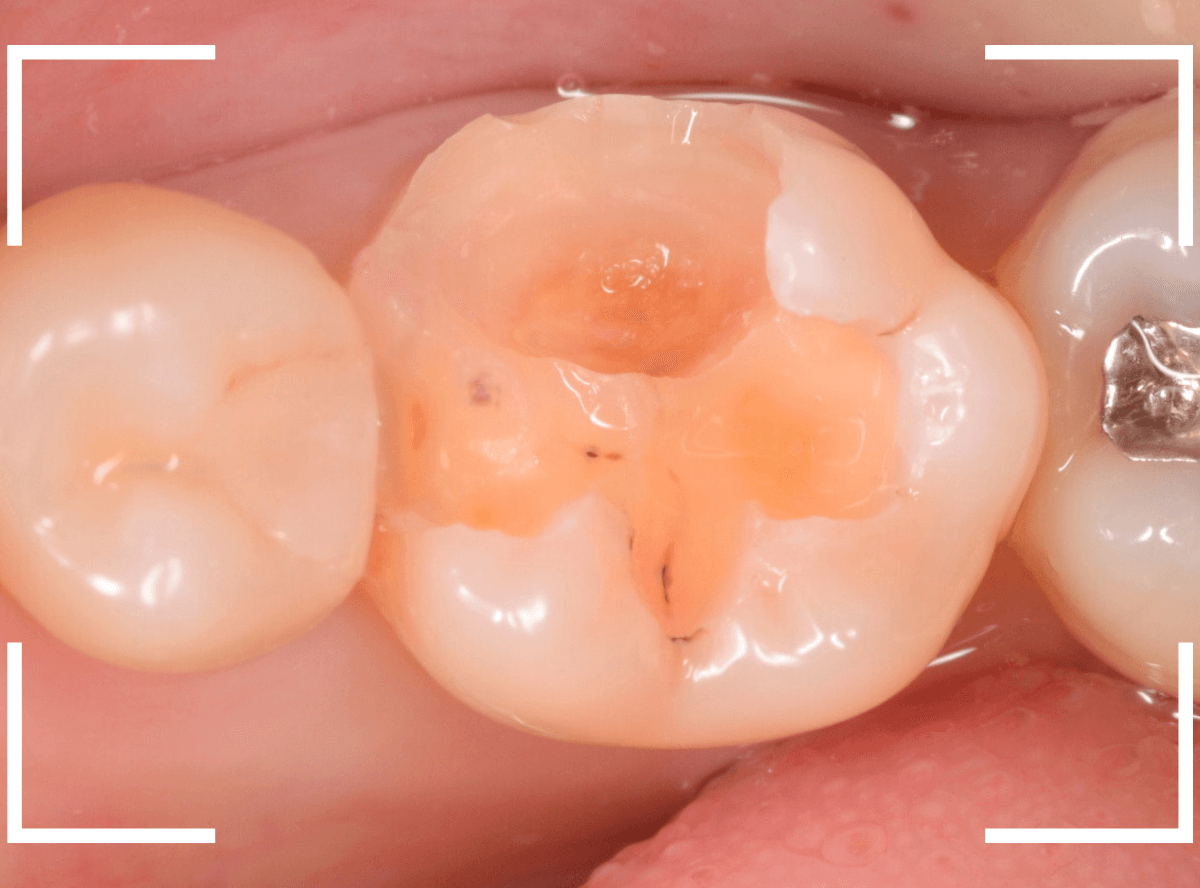

Case.12 検診で見つかった、インレーの下の深い虫歯

検診目的で来院された患者さんです。

特に気になるところもなかったですが、検査をすると、お口の中の色々な部分に虫歯が見つかりました。

その中の一か所、上の奥歯のインレーの下の虫歯です。

見た目だけでははっきりわかりませんでしたが、レントゲン写真で確認すると、インレーの下で虫歯になっているのがわかります。

インレーを除去して、治療を開始します。

ある程度、虫歯を除去したところで、う蝕検知液で確認します。

赤い部分が虫歯です。

やはり、レントゲン写真で確認した部分が深めの虫歯になっていたようです。

全ての虫歯を除去しました。

お薬をつめて痛みやしみが出ないか、しばらく経過観察しますが、おそらく大丈夫でしょう。

症状が出る前に、検診に来ていただいたことで最小限の治療で済みました。